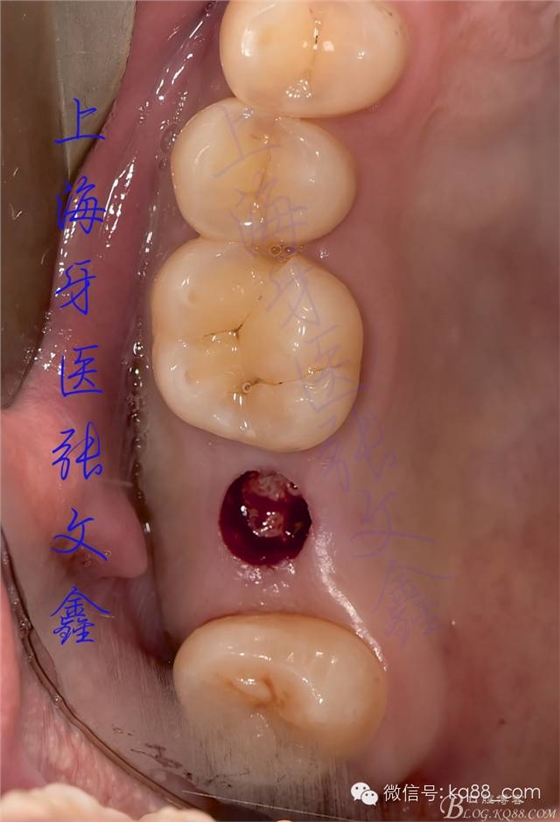

下面是患者手術(shù)的照片

術(shù)前口內(nèi)的照片